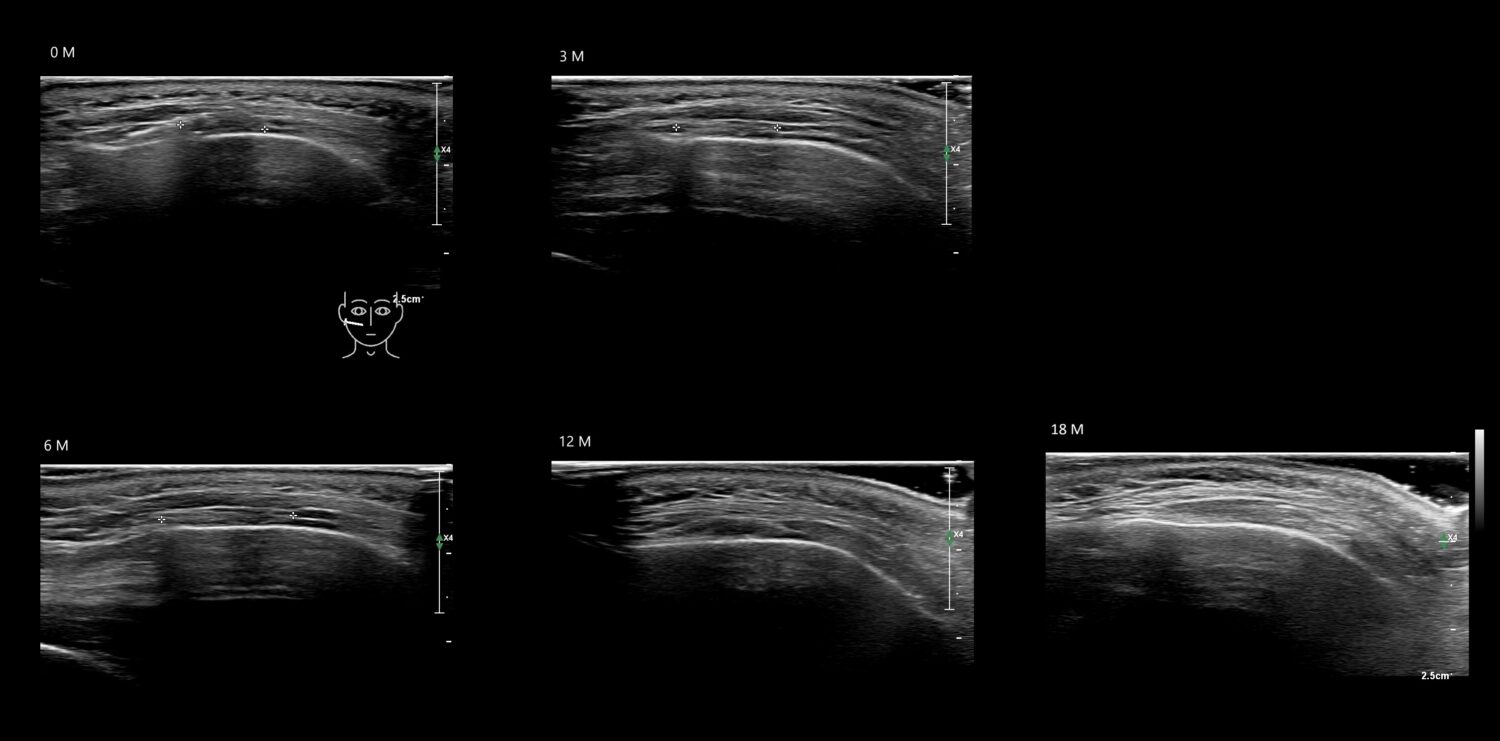

Fillers

Draw in the image on the right where the fillers are located. To check if your answer is correct, please click on the secondary image.